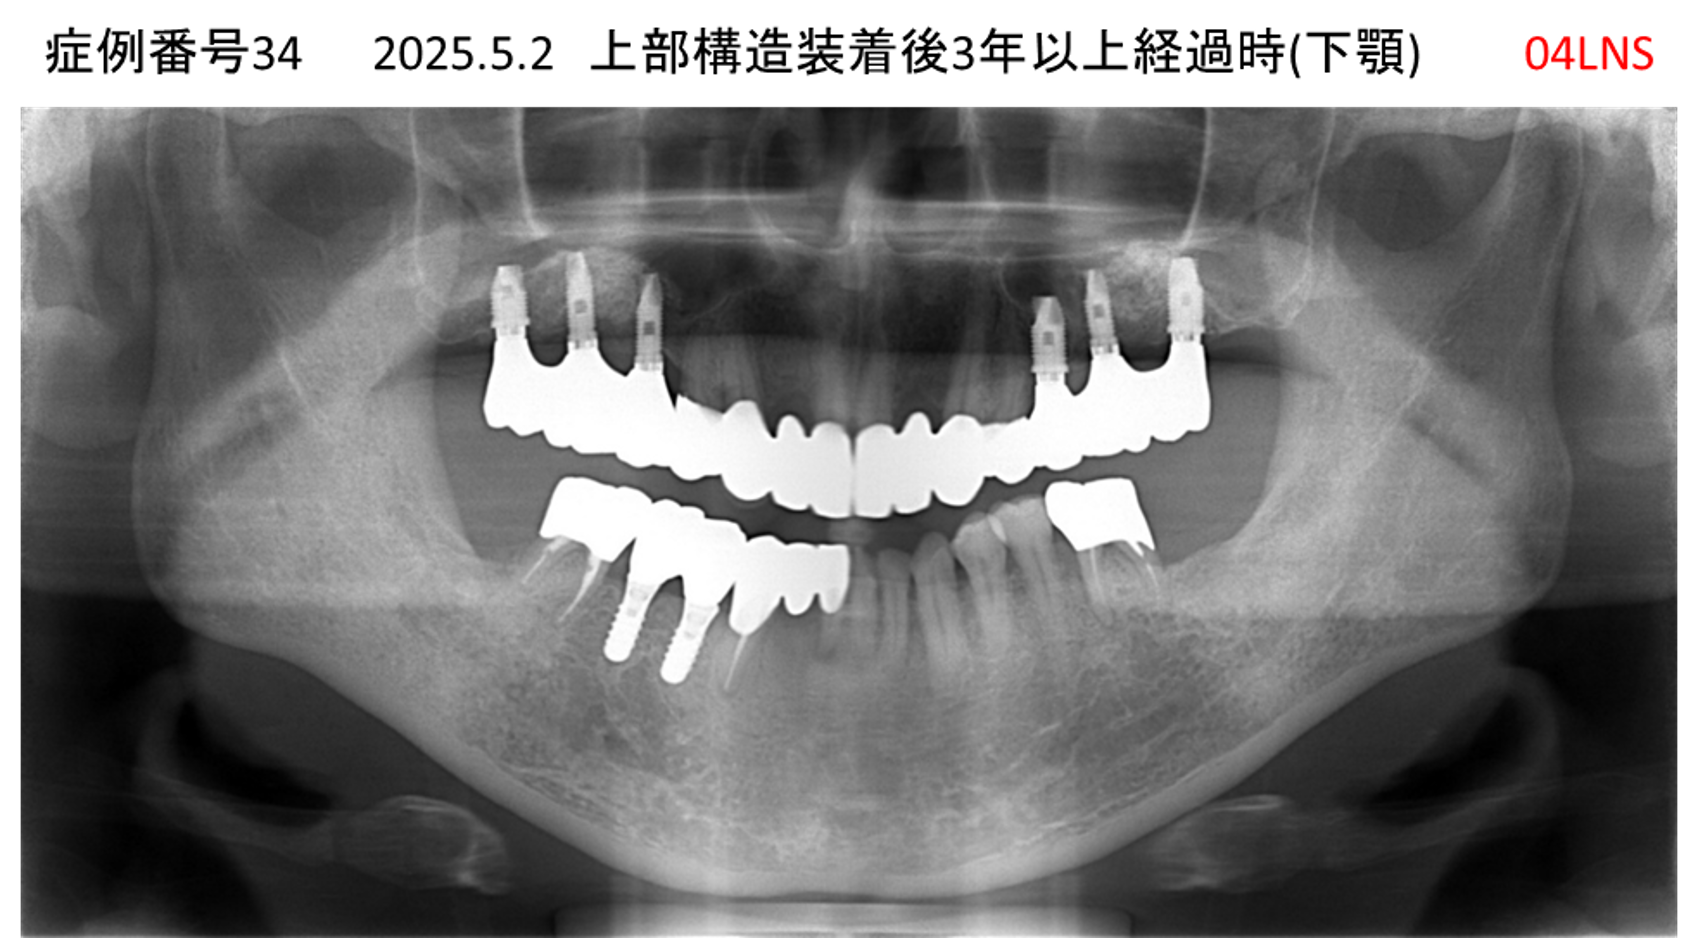

全く噛めない患者様のインプラント症例

| 治療名称 |

インプラントAGC |

| 治療費用 |

860万円+税 |

| 治療期間 |

12か月 |

| 患者さんの症状(主訴) |

全く噛めない、ごはんが後もに食べられるようになりたい、人前で口元を隠したくない |

| 治療内容 |

サイナスリフト、GBR、インプラント、AGC |

| 治療結果 |

しっかり噛めて踏ん張ることができる。食べ物をを選ばなくて済む、何でも食べられる、体重が増えた。見栄えがきれいすぎて自分じゃないみたい |

| 治療の注意点(リスク/副作用) |

インプラントが壊れたら再治療が必要 |